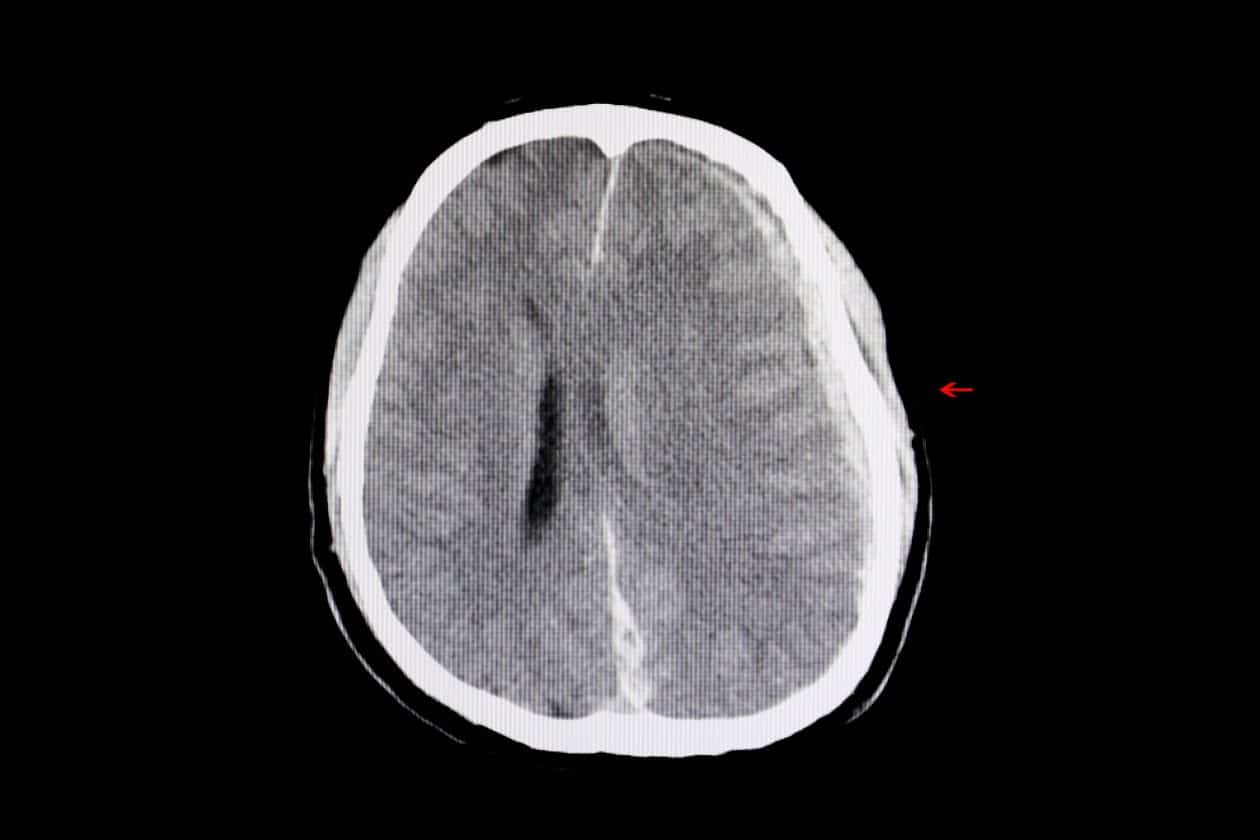

Lesiones cerebrales traumáticas después de un accidente

Las TBI pueden variar desde conmociones cerebrales leves hasta daño cerebral severo. Es fácil ignorar un golpe en la cabeza. Después de todo, es posible que al principio te sientas bien. Pero los síntomas pueden aparecer más tarde, complicando su recuperación. Los dolores de cabeza, los mareos o incluso los cambios de humor pueden indicar un problema más profundo. ¿Sabías que el cerebro es increíblemente vulnerable? Un ligero impacto puede alterar su funcionamiento normal.

Considere esto: está disfrutando de un día, tal vez andando en bicicleta. Un coche de repente se desvía y te caes. Es posible que un viaje a la sala de emergencias no revele ningún problema inmediato. Horas o días después, surge la confusión. Esa es la naturaleza complicada de las TBI. Pueden ser difíciles de alcanzar y requerir una evaluación exhaustiva. No pases por alto tu salud.

¿Alguna vez te has preguntado cómo un simple accidente puede provocar una lesión que cambie tu vida? Las lesiones cerebrales traumáticas (TBI, por sus siglas en inglés) pueden ser furtivas. No siempre aparecen de inmediato. A veces, los síntomas tardan en revelarse. Este retraso puede resultar frustrante y preocupante. ¿Puedes identificar los signos de una lesión cerebral traumática? Es vital saber qué buscar, especialmente después de un accidente en Avenal. Comprender estos síntomas puede permitirle tomar las medidas necesarias para su recuperación.

Algunos síntomas pueden incluso manifestarse días después del accidente. ¿De repente has empezado a tener dificultades para recordar detalles de tu día? O tal vez te sientas inusualmente ansioso o deprimido. Es fácil descartar esto como estrés por el accidente. Pero no descartes estos sentimientos. Podrían indicar una conmoción cerebral u otra lesión cerebral. El cerebro es un órgano complejo y su respuesta a una lesión puede variar ampliamente.

¿Ha considerado cómo las TBI pueden afectar su vida diaria? Las tareas simples pueden volverse desafiantes. Seguir una conversación puede resultar difícil o le resulta difícil encontrar las palabras adecuadas. Estos síntomas cognitivos pueden resultar frustrantes y aislantes. Pueden afectar su trabajo, sus relaciones y su bienestar general. Si nota tales desafíos, es fundamental buscar atención médica de inmediato.